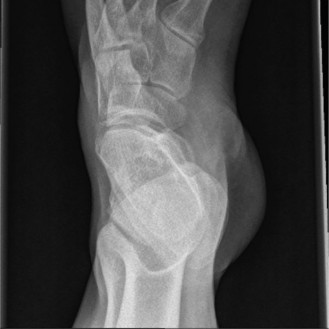

Plain Radiographic Evaluation

Anteroposterior, lateral, and mortise views of the right ankle demonstrated a highly comminuted intra-articular fracture of the distal tibia, extending into the tibial plafond. Significant articular depression and metaphyseal comminution were evident. There was an associated transverse fibular fracture approximately 5 cm proximal to the ankle joint, accompanied by lateral talar subluxation. The overall pattern was consistent with a high-energy axial load injury. The mortise appeared significantly widened, suggesting syndesmotic disruption and loss of the lateral collateral ligamentous restraint.

Computed Tomography and Three Dimensional Mapping

Following initial stabilization and application of a spanning external fixator, a high-resolution Computed Tomography scan of the ankle with fine 1mm axial cuts and multiplanar reconstructions (coronal and sagittal) was obtained. CT imaging is mandatory in the evaluation of pilon fractures to delineate the extent of articular involvement, fragment displacement, and comminution for precise pre-operative planning.

The CT confirmed an OTA/AO 43-C3 pilon fracture with extensive articular depression and displacement of the central die-punch fragments. The articular surface was shattered into the classic three primary fragments described by Topliss et al., the medial malleolus, the anterolateral (Chaput) fragment, and the posterolateral (Volkmann) fragment, alongside severe central impaction. The sagittal reconstructions revealed a 12mm articular step-off and a large central void in the metaphyseal bone where the cancellous bone had been crushed by the impacting talus. The coronal views highlighted the severe varus angulation of the distal tibia and the impaction of the medial shoulder of the talus into the medial plafond.